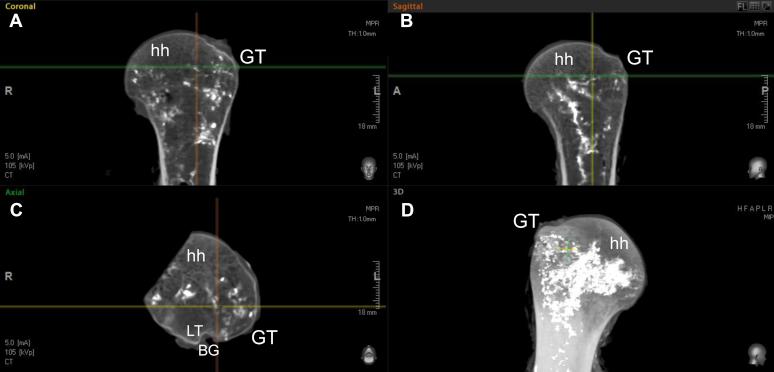

Formalin preserved specimens were used to measure ACHA length, ACHA length in the bicipital groove (BG), the length of the ascending branch of the ACHA, the penetration point of the ascending branch of the ACHA at the greater tuberosity (GT), and the penetration point of the ascending branch PCHA at the GT. Fresh specimens were used to identify the intraosseous vascular network by both the ACHA and PCHA by injecting a contrast medium using a high-resolution microfocus computed tomography. Specimens were then dissected to expose where the branches of the ACHA and PCHA penetrate the bone, and a small section of the medial head was removed to visualize dye penetration of the cancellous bone.

Seven variations for the course of the ACHA were observed. In 36%, the ACHA runs posterior to the BG and posterior to the long head of biceps tendon, and splits into the anterolateral ascending and descending branch. The ascending branch enters the medial wall of the GT. Microfocus computed tomography demonstrated that the intraosseous branch of the ascending branch of the ACHA runs within the GT in a medial direction from its penetration point just along the lateral edge of the BG. Intraosseous accumulation of contrast within the GT supply occurs more toward the inferior aspect of the HH, and the anterior-superior and superior-medial aspect of the HH is not perfused. This region is a high-risk zone for avascular necrosis.